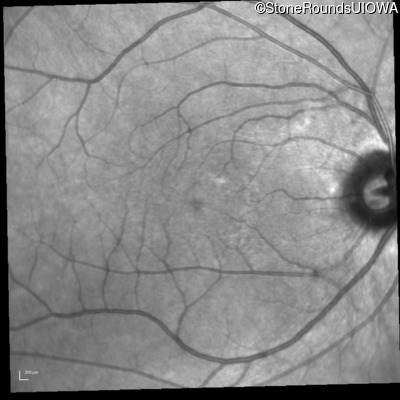

Infrared Fundus Photograph - Right - 20/20

Exemplar

Infrared Fundus Photograph - Left - 20/20 -2